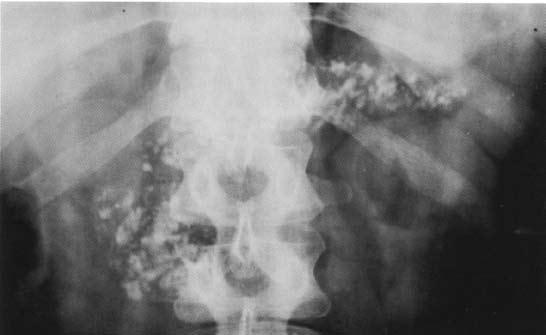

Обзорная рентгенография верхнего отдела брюшной полости имеет больше академическое значение в диагностике ХП, однако, характерные изменения удается выявить лишь у больных с выраженным обызвествлением паренхимы железы и/или достаточно крупными обызвествленными конкрементами в панкреатическом протоке (рис. 131).

Рис. 131. Обзорная рентгенограмма органов брюшной полости (поджелудочной железы) при хроническом кальцифицирующем панкреатите. На снимке видны крупные кальцинаты в проекции поджелудочной железы на всем протяжении (во всех отделах поджелудочной железы)